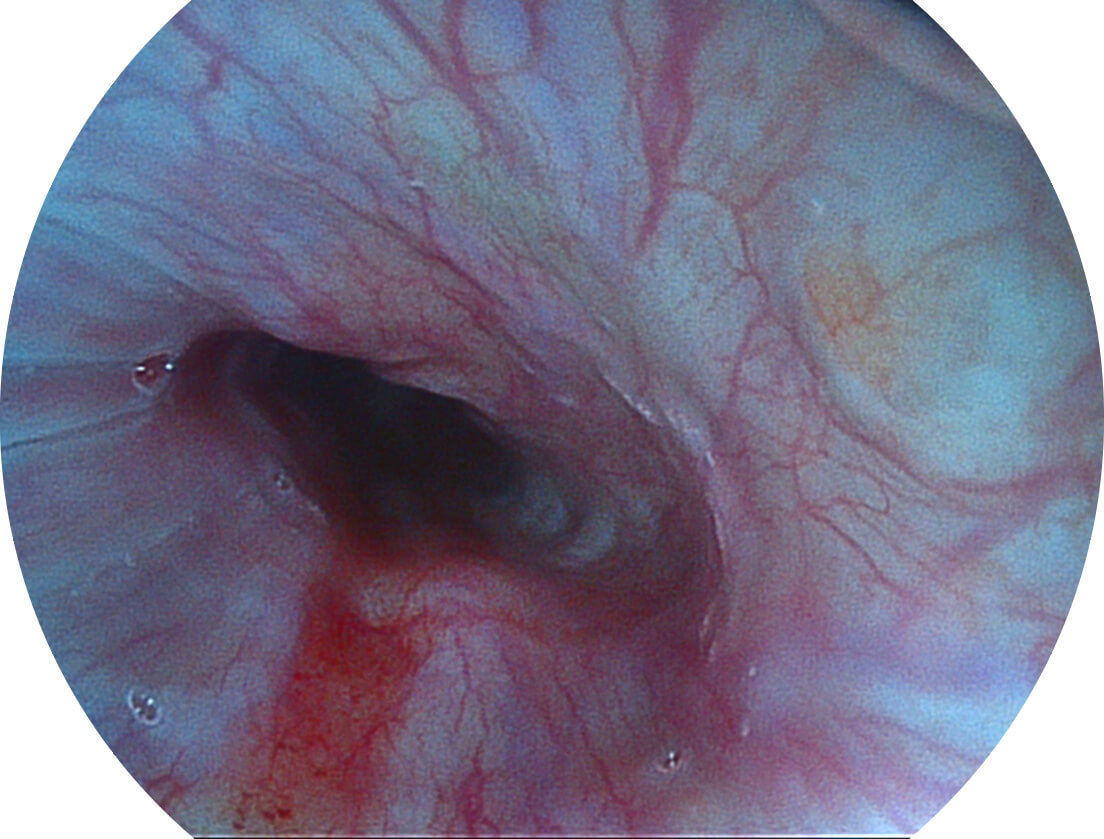

Versatile Intelligent Staining Technology, VIST

强调浅层黏膜结构的同时,保证照明亮度和提升浅层微血管与中层血管颜色对比度,病变边界更清晰。

血管对比度分布光谱曲线

VIST光谱